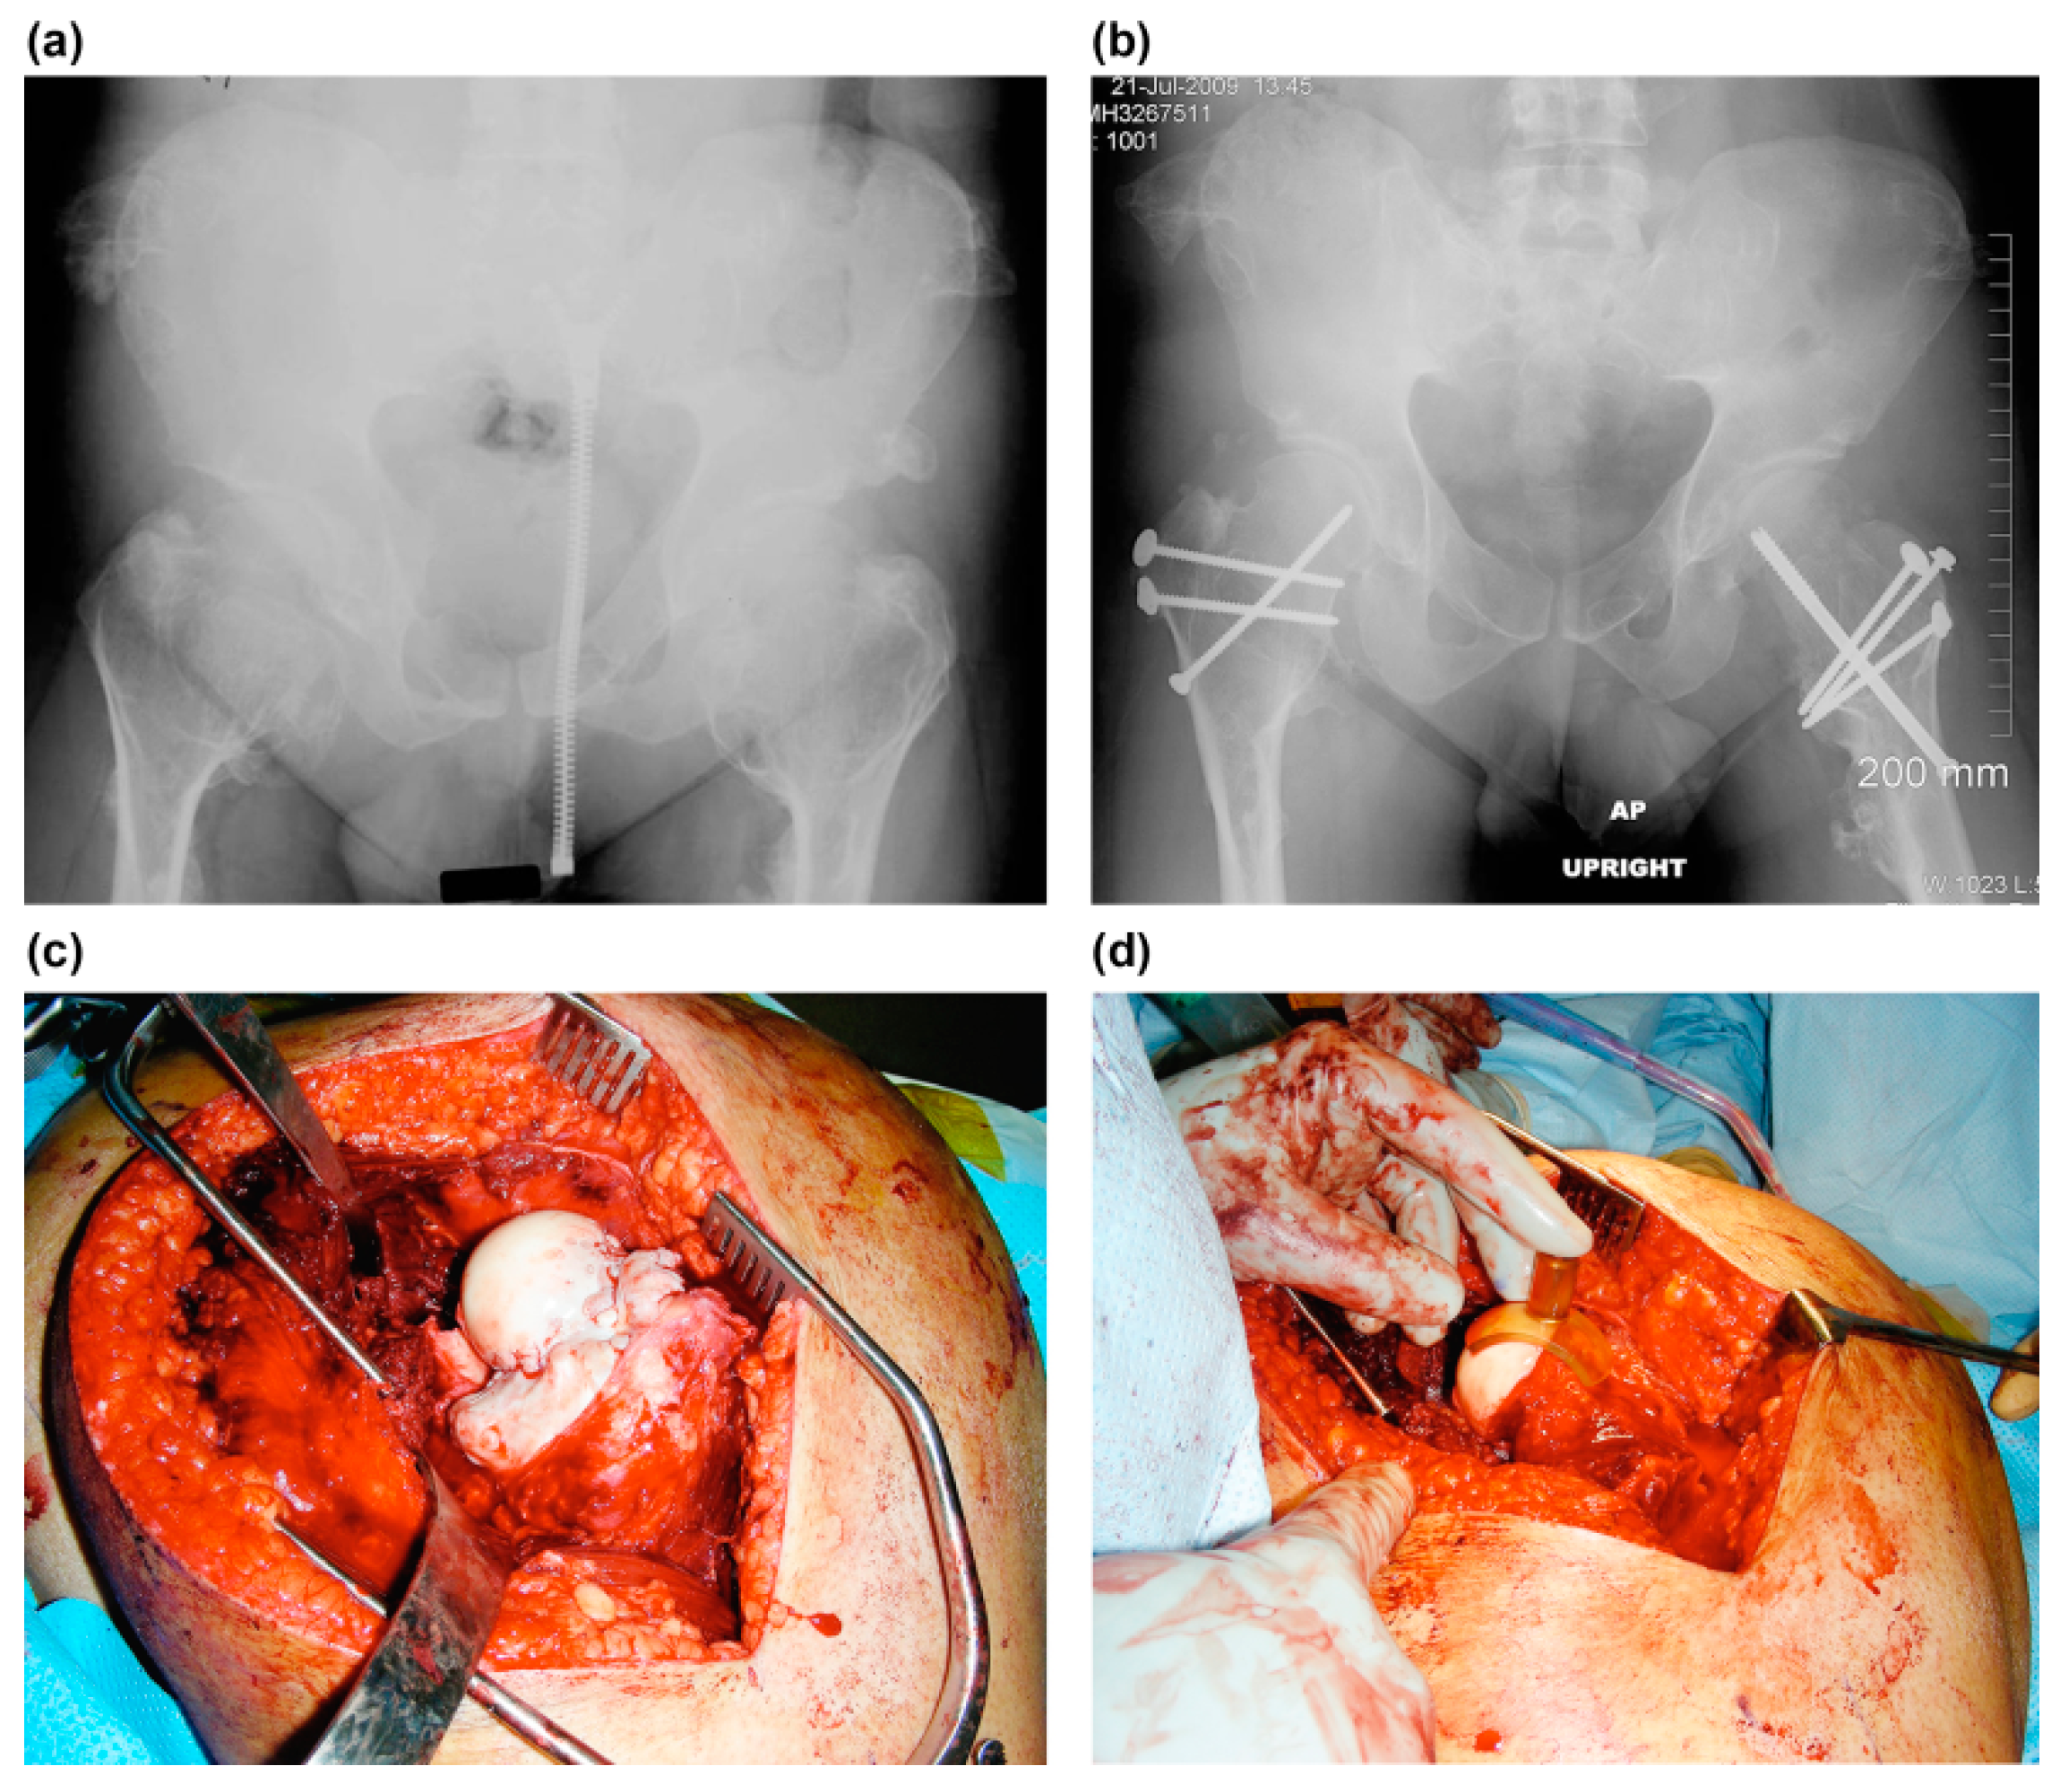

Figure 3.

The images show the case of a 23-year-old man with symptomatic bilateral femoroacetabular impingement pain and limitation of motion (case no. 5). (a) Preoperative anteroposterior radiograph shows a large bump at the medial side of the femoral neck. Neck–shaft angle of the femur was within tolerable range (Rt, 140; Lt, 150). The containment of the hip was normal. (b) Postoperative anteroposterior radiograph of the hip. Mediolateral neck–shaft ratio improved from 6.7 to 1.6 on the right hip, 3.6 to 1.7 on the left hip. A cortical or cannulated screw was inserted through the femoral neck to prevent femoral neck fracture and the osteotomized greater trochanter was fixed with two-three 3.5 mm cortical screws. (c) Intraoperative photograph of the left hip. (d) The osteochondroplasty of the femoral neck can be performed with small osteotomes and a high-speed burr. When the resection is satisfactory, a special template (spherometer gage) can be used to check the sphericity of the remaining femoral head. The neck–shaft ratio improved from 3.6 to 1.7 mediolaterally and 2.7 to 1.3 anteroposteriorly.